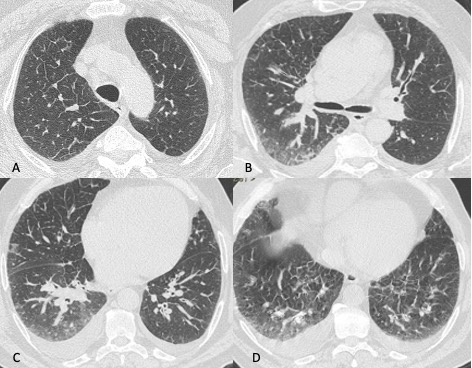

Figura 5: Uomo di 68 anni immunocompromesso giunge al Pronto Soccorso per IRA. La TCAR eseguita all’ingresso (immagini assiali A-B-C e la ricostruzione MPR sul piano coronale D) mostrano "vetro smerigliato" diffuso e simmetrico in entrambi i polmoni con relativo risparmio delle aree sub-pleuriche solo in alcune zone nel polmone. L’ipotesi diagnostica formulata è stata quella di polmonite interstiziale. Le indagini di laboratorio hanno in seguito rivelato che l’agente patogeno responsabile del quadro flogistico era lo Pneumocystis Jirovecii. La diagnosi differenziale tra le varie cause di iperdensità parenchimale nei pazienti con IRA non è semplice soprattutto quando le alterazioni sono molto estese e diffuse.

Figura 6: Donna di 73 anni giunge in Pronto Soccorso per febbre, dispnea e dolore addominale. La TCAR eseguita due giorni dopo il ricovero (immagini assiali A-B-C e ricostruzione MPR sul piano coronale D), mostra la presenza nel lobo superiore sinistro di un’area di aumentata densità con aspetto prevalentemente consolidativo ed in parte a "vetro smerigliato" con broncogramma aereo nel contesto, reperti tipici di polmonite batterica. Il BAL eseguito in seguito conferma l’ipotesi di polmonite batterica, l’agente eziologico isolato è la Legionella.

Figura 7: Uomo di 67 anni ricoverato per polmonite batterica confermata anche dalla radiografia del torace eseguita all’ingresso in Pronto Soccorso. In considerazione dell’aggravarsi del quadro clinico viene richiesto un approfondimento diagnostico tramite TCAR (immagini assiali A-B ed MPR coronale C ed MPR sagittale D), da cui si evidenzia la presenza nel lobo inferiore dx di un area di aumentata densità con aspetto consolidativo nel cui contesto si osservano multiple aree a densità aerea, reperti compatibili con ascesso polmonare, possibile complicazione della polmonite batterica.

Figura 8: Donna di 62 anni con infezione da botulino e polmonite ab-ingestis. La TCAR eseguita all’ingresso al Pronto Soccorso (MPR coronale A e immagini assiali B e C) mostra la presenza di aree di aumentata densità con aspetto in parte consolidativo ed in parte a "vetro smerigliato" in entrambi i lobi inferiori e nella lingula con la presenza di stria atelettasica nella lingula.